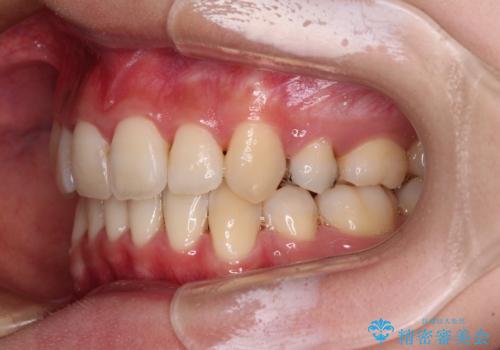

- 前歯の叢生と八重歯を気にして来院された患者様です。

叢生が強く、奥歯の咬合も左右差が大きかったため、上下左右4本を抜歯して、ワイヤー矯正を行うこととしました。

20歳前後と年齢が若かったため、非常にスムーズに歯列が整い、1年半をかけずに治療を終えることができました。